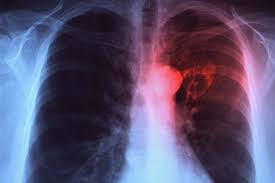

Because there are some important organs below your right breast including the gallbladder right kidney part of the lung and liver some people worry that this pain is a symptom of heart disease but the heart is located on the left side of your chest and the pain below the right breast is often not related to the heart.

Sharp pain on right side of chest under breast. The book clinical methods says that chest pain is one of the most common reasons why a person visits their doctor. Another symptom usually experienced by patients is a sharp pain while laying down or when they take a deep breath. Here are some possible medical conditions associated with it.

Sometimes this pain travels to the shoulder and can be felt under the shoulder blade. Inflammation of the liver can cause popping in the chest as well as pain in the right shoulder or pain in the right side of the rib cage and back. Possible causes of sharp pain under right breast.

Similarly right side chest pain may be due to hepatitis which is a disease that causes swelling and inflammation of the liver. Some women may experience a sharp pain under their right breast that comes and goes. Armpit pain underarm pain can be caused by a number of things that include pinched nerve pregnancy cancer swollen armpits and lymph nodes muscle pain breastfeeding waxing cystic pimple cancer among other causes this pain in armpit can affect female and male adults and children and it could be sharp shooting or dull constant or comes and goes on the right or left armpit or.

Others may experience it every time they take a breath. Pain under the right breast is rarely a cause for concern and often results from muscles strains or minor injuries. The pain under your breast will often get worse after eating.